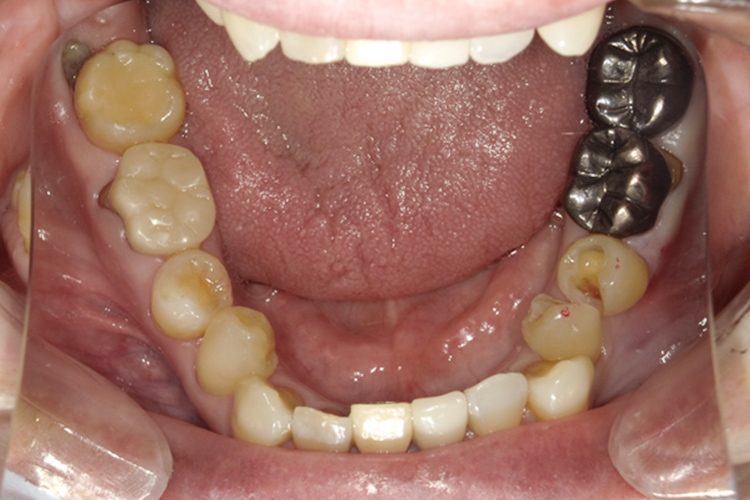

治療前

治療後